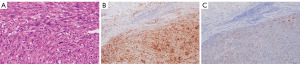

A 72-year-old man was referred to Nippon Medical School Tamanagayama Hospital with suspected lung cancer. He had no symptoms and no notable past medical history, but 25 pack-years of smoking history. Preoperative 18F-fluorodeoxyglucose positron emission tomography/computed tomography (18F-FDG-PET/CT) imaging showed intense uptake in an 18 mm nodule in the left upper lobe of the lung, but the transbronchial biopsy showed no evidence of malignancy. Brain magnetic resonance imaging showed no metastatic lesions. The clinical stage was cT1bN0M0, stage IA2. The patient underwent left upper lobectomy and mediastinal lymphadenectomy and was diagnosed with PPC (Figure 1A-1C). The pathological stage was pT3N0M0, stage IIB.